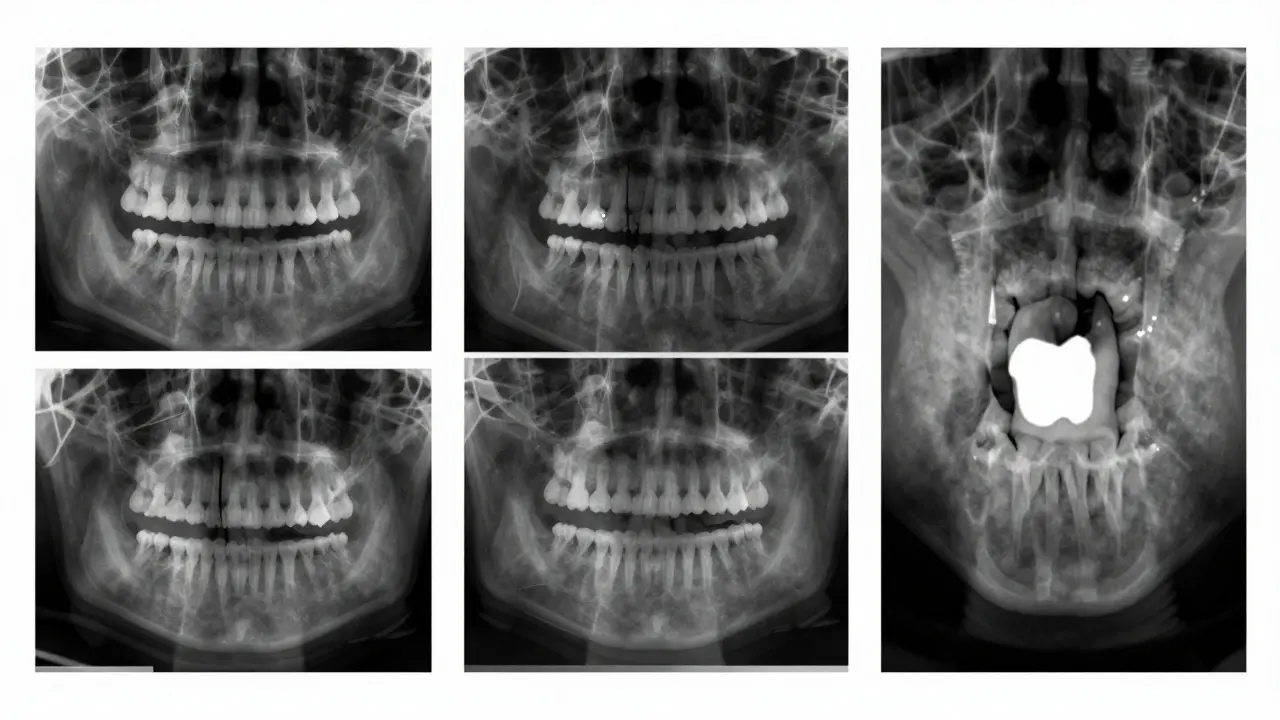

Sada digitálních rentgenových snímků s různými stádii karies a zubními plombami.

Nejčastěji se při diagnostice karies používají dva typy rentgenů:

• Paralelní (bitewing) rentgen - to je ten, kde držíte malý papírek s filmem mezi zuby. Ten ukazuje horní a dolní zuby najednou, a hlavně - jejich kontaktové plochy. Tady se vidí 90 % mezizubních kazů. Je to základní snímek, který se dělá při každé preventivní prohlídce.

• Periapikální rentgen - ukazuje celý zub od špičky kořene až po vrchol korunky. Používá se, když se podezřívá karies hluboko u kořene, nebo když je potřeba zkontrolovat, jestli kaz dosáhl na nerv.

Moderní zubní ordinace už téměř všechny snímky dělají digitálně. Tyto snímky mají o 80 % nižší dávku záření než staré filmové a umožňují zubaři zvětšovat obraz, upravovat kontrast a zvýrazňovat tmavé oblasti. To znamená, že i velmi malé počáteční karies se dají detekovat dříve, než se stane problémem.